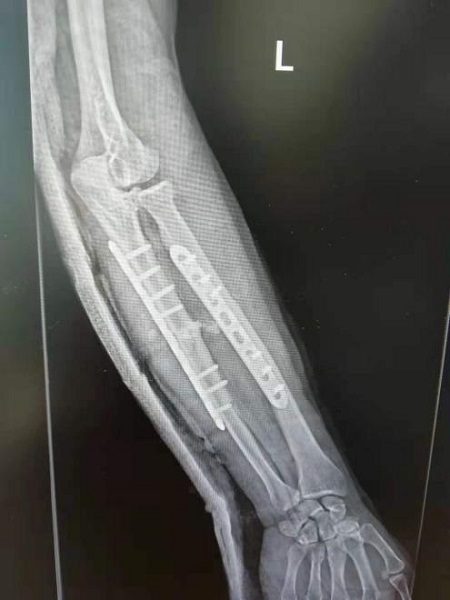

为了让断肢的功能尽量恢复,抢救小组将在对残肢伤口清创后,标记每一根血管、神经、肌腱,将具备再植条件的血管、神经、肌腱一一找出,将尺骨桡骨短缩对合;再使用钢板螺钉固定骨端,吻合肌腱、神经、动静脉血管,对患者的伤情使出“绣花针功夫”,仔细谨慎,不容任何偏差。

图/术后14天,重焕生机的前臂